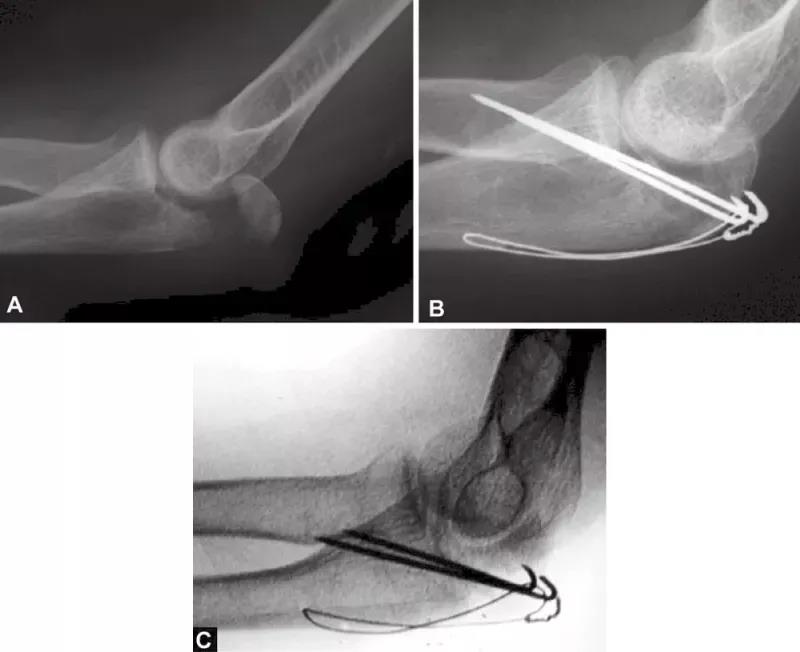

图2A~C关节面部分压缩非常不易觉察。有经验的医生会注意到鹰嘴曲线的变窄从而推断出压缩部分的存在。术中斜位X线片检查压缩骨折仍隐匿,仅在术后的X射线中越来越明显